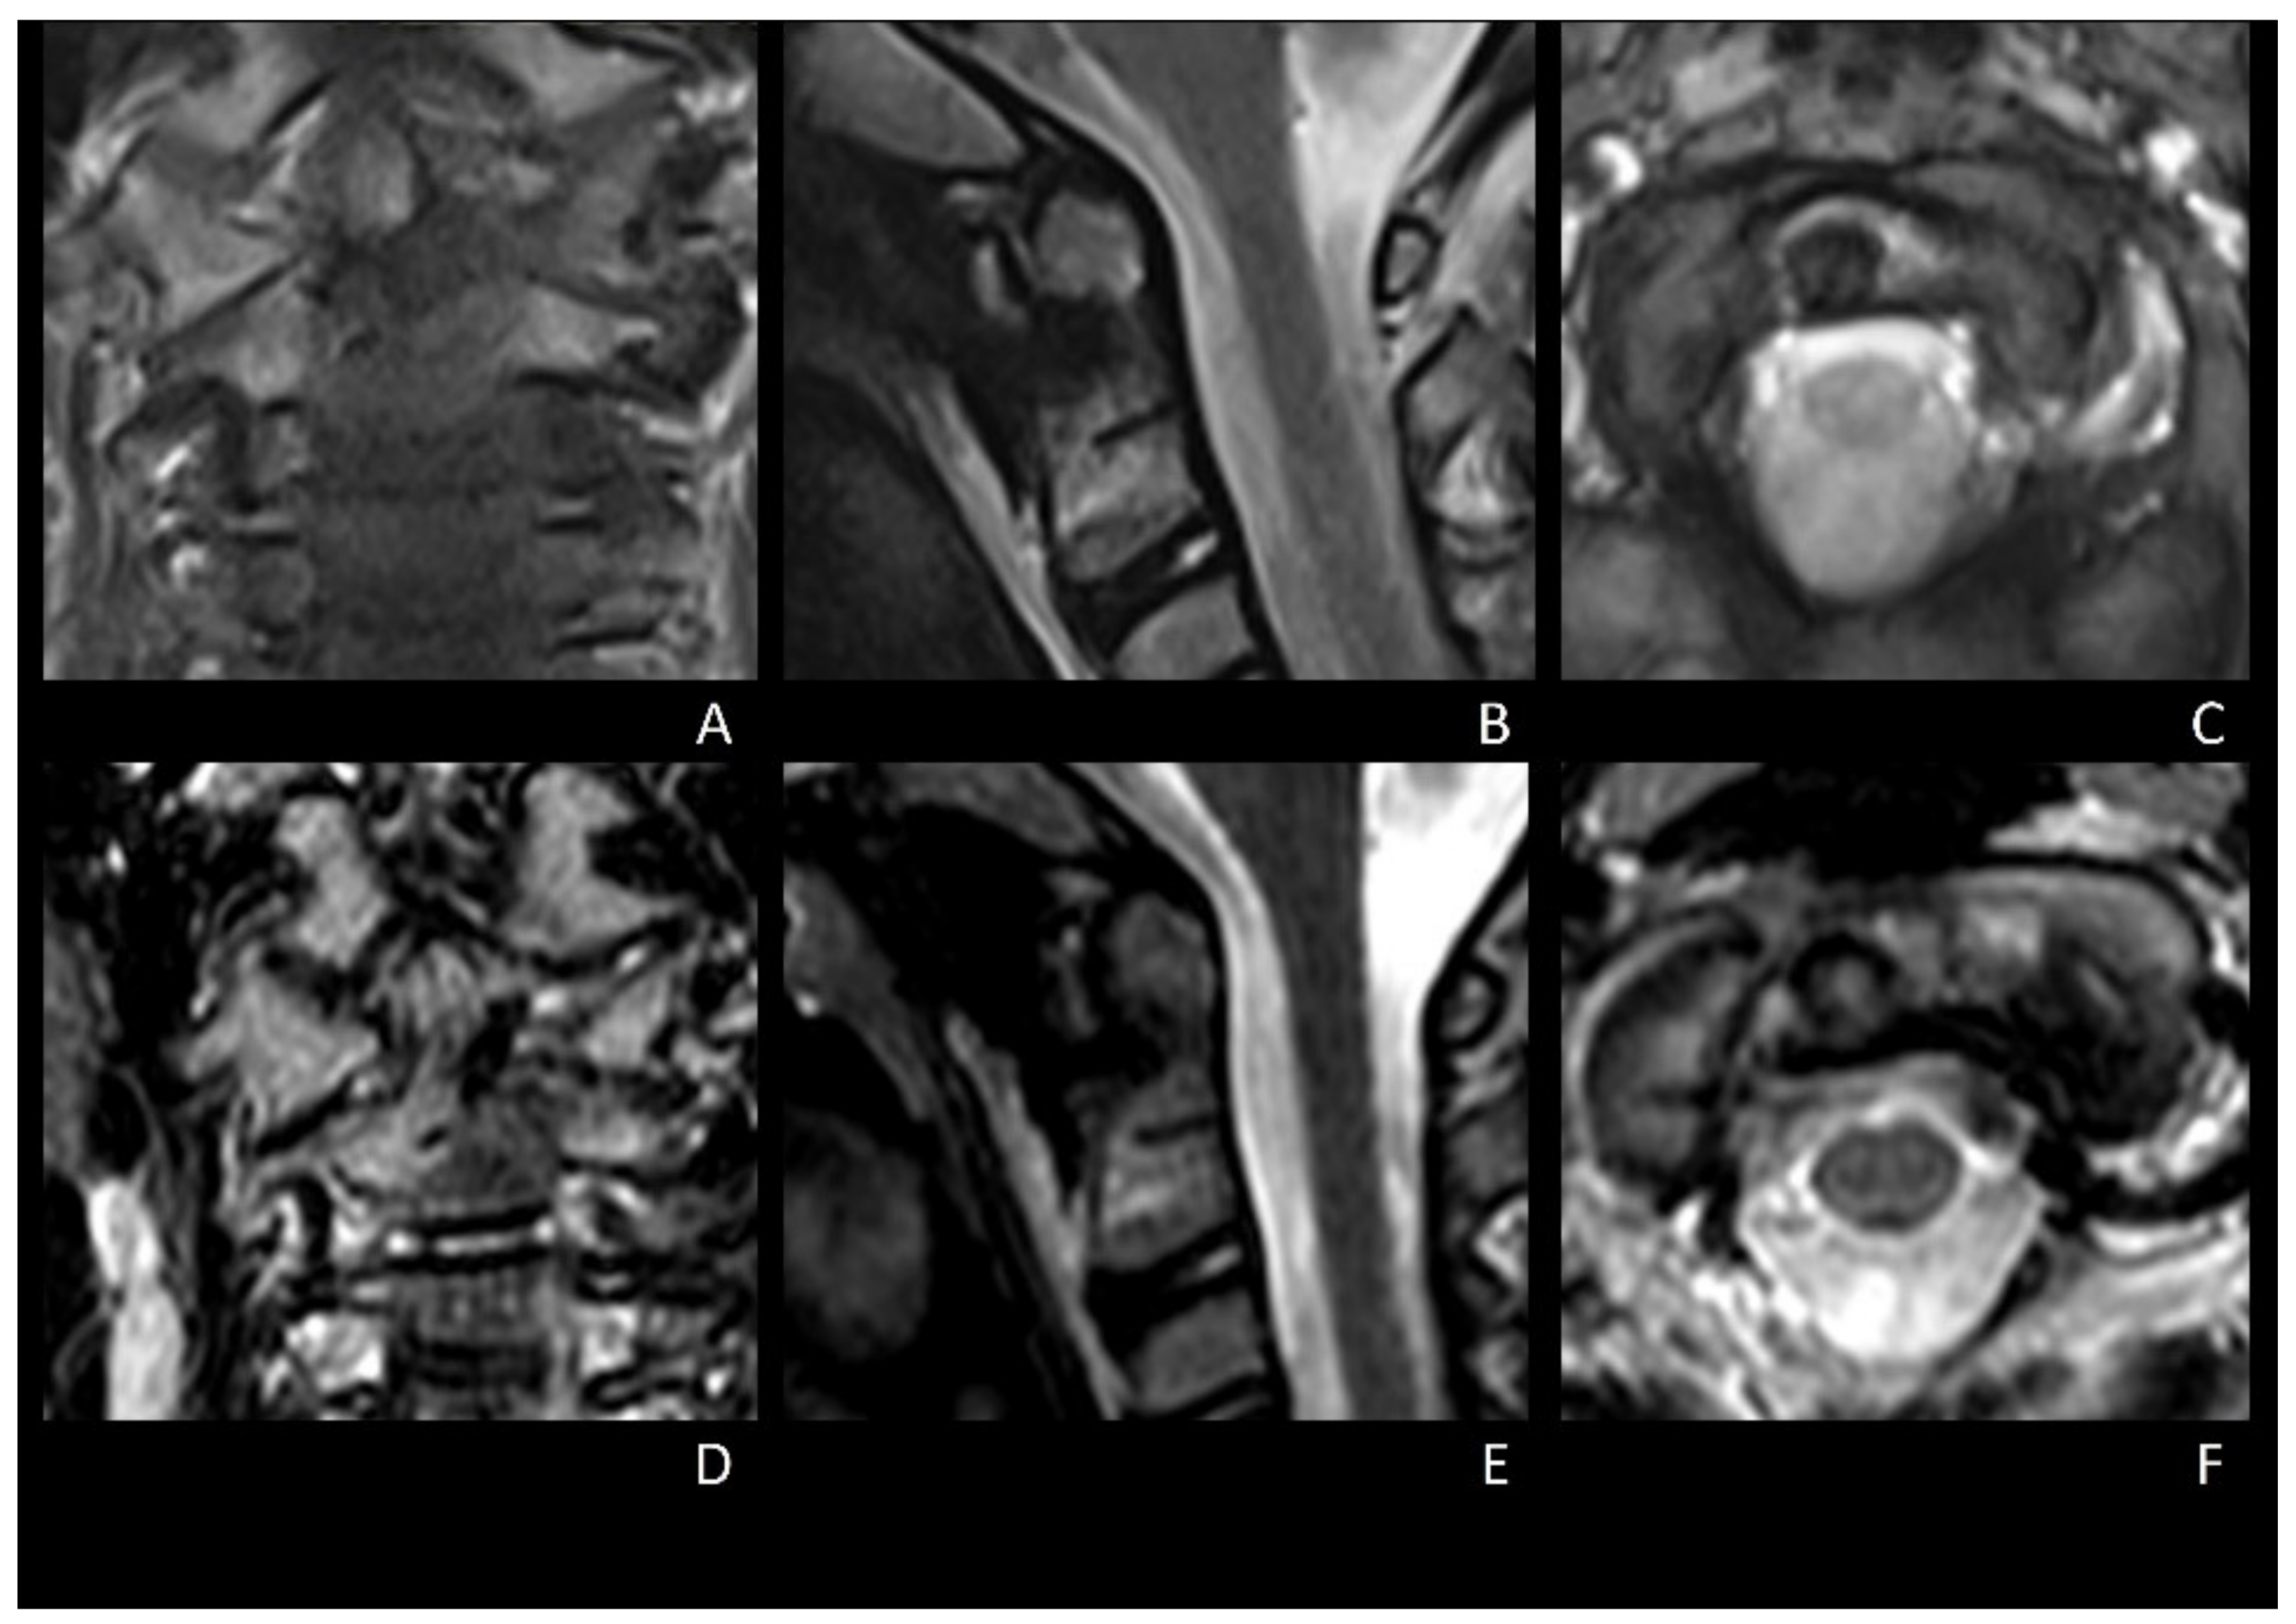

2.1. Technical Note

2.1.2. Surgical Procedure

2.1.3. Post-Operative Course and Follow-Up